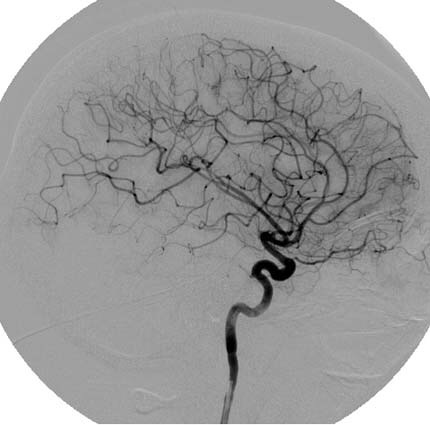

Dr. Caio came last night and said ” I am sad that Getulio is not here to know what you have. He never asked you to do an angiography because it is an invasive exam, he did all the work and this time it became clear that you needed to do this exam. You have cerebral vasculitis. It is not a symptom it is what is behind everything ”